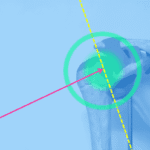

Figura 4. Entidades clínicas definidas para el dolor inguinal.

1 (azul): Relacionado con los aductores. 2: Relacionado al recto abdominal. 3 (verde): Relacionado con el psoasilíaco. 4 (morado):Relacionado con la ingle. 5 (amarillo): Relacionado con el pubis.

(Weir A, Brukner P, et al. Doha agreement meeting on terminology and definitions in groin pain in athletes. Br J Sports Med 2015; 49: 768–74).

ebtc.ie/groin-pain-in-athletes/